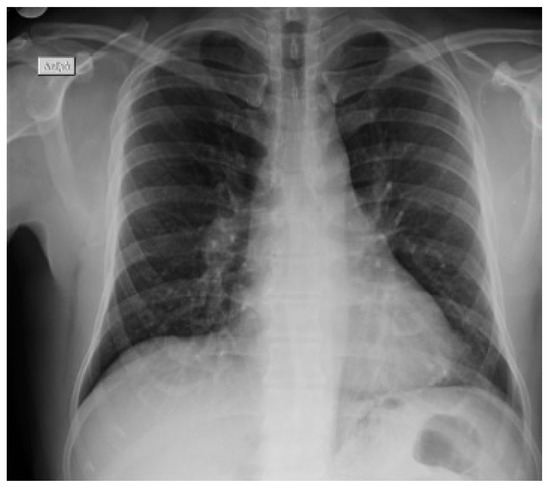

He was subjected to isolation, pending further investigation. Lung auscultation demonstrated a mildly reduced intensity of breath sounds mainly at the bases. The blood tests showed normal white blood cells (5.690/μL, 74.8% neutrophils and 14.1% lymphocytes), increased erythrocyte sedimentation rate (ESR 35 mm per hour) and normal biochemical testing (glucose, urea, creatinine, electrolytes and liver function tests). The arterial blood gas sample analysis showed a respiratory alkalosis with a pH 7.461, a pO2 of 82.8 mmHg, a pCO2 of 25 mmHg, an O2 saturation of 97% and a HCO3 of 18 mmol/L, while the lactate level was of 0.8 mmol/L). The chest X-ray depicted an increase in overall lung markings and elevation of the right hemidiaphragm with no consolidation or other findings (Figure 2).

Figure 2. Patient’ s X-ray after he was admitted to the emergency department.